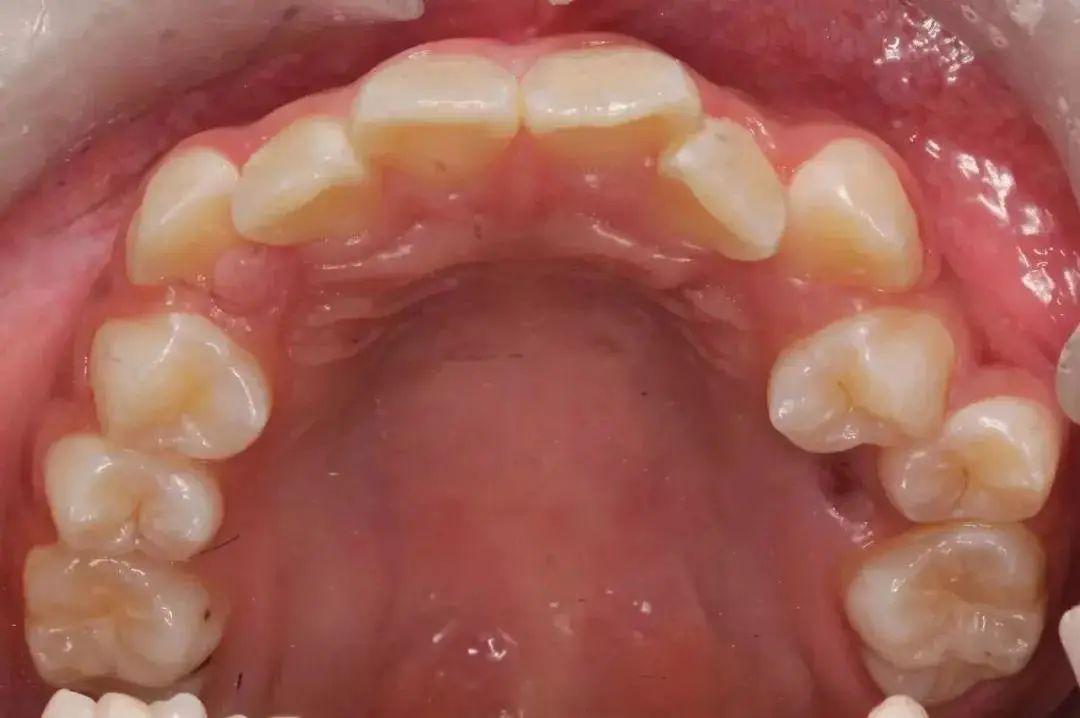

牙齿矫正不一定要拔牙,但需要拔牙的案例很常见(大约75%的比例)。因为随着饮食越来越精细,下颌骨越来越小,无法整齐排列32颗牙齿,造成龅牙、牙齿拥挤等后果。

特别是对于牙齿拥挤、大龅牙等情况,如果不拔牙,很难得到一个令人满意的治疗效果。且该拔牙的病例不拔牙,会更加容易反弹,导致矫正失败。

1、矫治拥挤:牙齿严重拥挤的患者,拔牙后有了空隙,可以将拥挤的牙齿排齐,使矫治效果稳定,畸形不易复发。